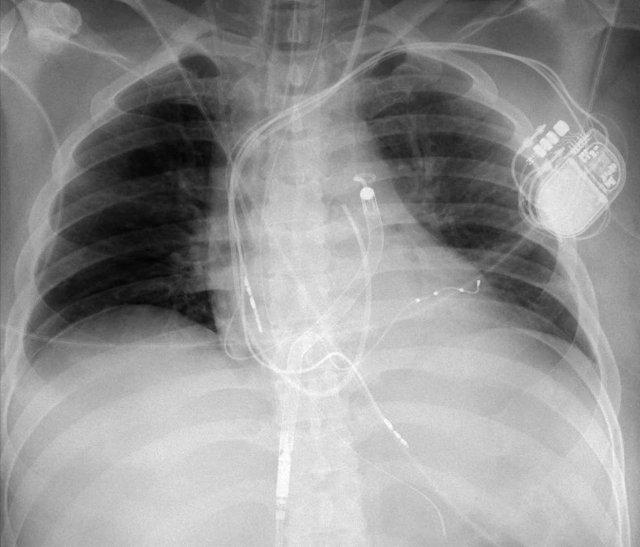

Hình ảnh dưới đây cho thấy một bệnh nhân được đặt LVAD.

Ống cannula dòng vào được đưa vào mỏm tim và ống cannula dòng ra (không cản quang) được nối với động mạch chủ lên.

Cũng cần lưu ý sự hiện diện của máy ICD ba điện cực với hai cuộn sốc điện và các clip ghép động mạch vú trong trái (LIMA) từ lần phẫu thuật trước.

Các thiết bị hiện đang được lắp đặt bao gồm:

- Ống thông tĩnh mạch trung tâm đặt tại tĩnh mạch cảnh trong bên phải.

- Ống thông dạ dày (ống nuôi ăn) được đặt vào dạ dày.

- Ống nội khí quản được đặt phía trên carina.

- Máy tạo nhịp tim 3 điện cực với các điện cực đặt tại tâm thất phải (RV), nhĩ phải (RA) và tâm thất trái (LV).

- Ống thông Swan-Ganz đặt trong động mạch phổi.

- Thiết bị Impella bên phải đặt trong động mạch phổi, được sử dụng để giảm tải cho tâm thất phải trong bối cảnh suy tim phải.

- Các điện cực điện tâm đồ (EKG) đã được gắn vào vị trí.